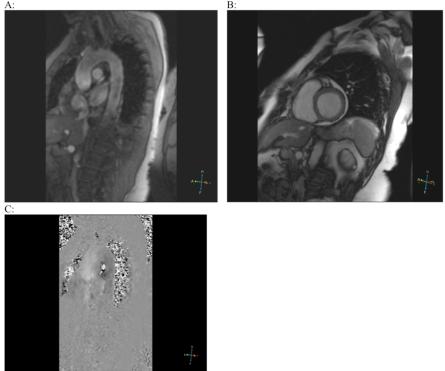

Wegener's granulomatosis (WG) is one of the most common small- and medium-sized necrotizing vasculitides that mainly affects the upper and lower respiratory tract and the kidneys. Cardiac manifestations in WG are relatively rare, and their role and place among different causes of mortality remain largely unknown. Substantially increased number of reports describing involvement of all structures of the heart, which underlie conduction disturbances, valvular disease, ischemic heart disease and other potentially serious conditions, underscores importance of comprehensive cardiovascular investigations and monitoring of patients with WG. The majority of previous reports and our current observation distinguish coronary vasculitis and thrombosis as a cause of myocardial ischemia and cardiovascular co-morbidities in WG. It seems plausible that inflammatory processes in this disease, like in some other systemic vasculitidies, do not predispose to accelerated atherogenesis. However, characteristic small- and medium-sized vasculitis still can manifest as myocardial ischemia and infarction. We overview diverse cardiac manifestations and present our own rare case of angina in the oligosymptomatic debut of WG. Importantly, in this case, coronarography failed to reveal atherosclerotic disease or thrombotic occlusion. However, magnetic resonance imaging (MRI) with adenosine test revealed subendocardial ischemia. As a result of immunosuppressive therapy with a steroid and cyclophosphamide, myocardial ischemia disappeared.

韦格纳肉芽肿病(WG)是最常见的中小血管坏死性血管炎之一,主要累及上、下呼吸道及肾脏。WG的心脏表现相对少见,其在不同死因中的作用和地位仍 largely unknown。大量报告描述了心脏所有结构受累,这些结构是传导障碍、瓣膜病、缺血性心脏病及其他潜在严重疾病的基础,这凸显了对WG患者进行全面心血管检查和监测的重要性。先前的大多数报告以及我们目前的观察结果都将冠状动脉血管炎和血栓形成视为WG中心肌缺血和心血管合并症的原因。在这种疾病中,与其他一些系统性血管炎一样,炎症过程似乎不太可能导致动脉粥样硬化加速发展,这似乎是合理的。然而,典型的中小血管炎仍可表现为心肌缺血和梗死。我们概述了各种心脏表现,并展示了我们自己遇到的1例罕见的WG寡症状初发时的心绞痛病例。重要的是,在该病例中,冠状动脉造影未发现动脉粥样硬化疾病或血栓闭塞。然而,腺苷试验的磁共振成像(MRI)显示心内膜下缺血。经过类固醇和环磷酰胺的免疫抑制治疗,心肌缺血消失。